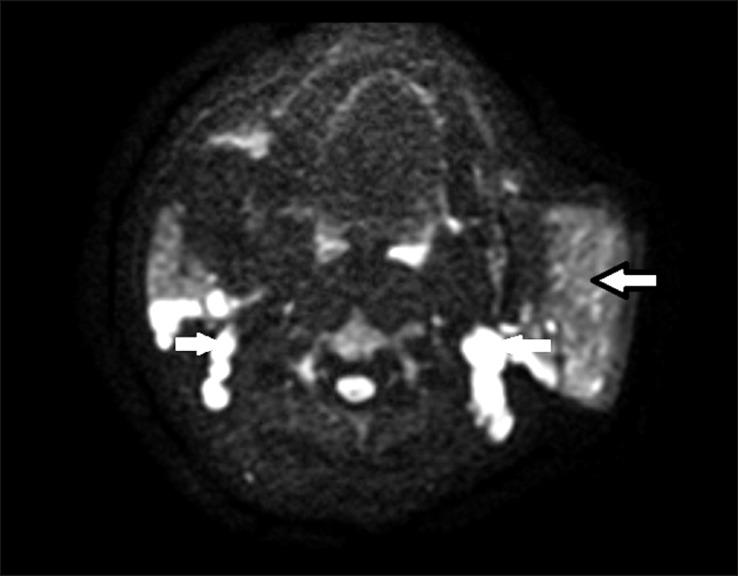

Kimura disease is an uncommon, benign, chronic, idiopathic disease that is seen mainly in the Asian population, particularly in females. It mainly affects the salivary glands and in particular parotid and cervical lymph nodes. So far, the diagnosis of Kimura disease has been based on histopathology. We hereby report of a confirmed case of Kimura disease and provide a detailed explanation of its imaging features with a special emphasis on diffusion-weighted imaging, as diffusion sequences may help distinguish Kimura disease from malignancy.

A middle-aged female patient presenting with a history of multiple chronic neck swellings was thoroughly evaluated by ultrasound (US), computed tomography (CT), and magnetic resonance imaging (MRI). The imaging findings included gross enlargement of the left parotid gland, a focal lesion in the right parotid gland, and cervical lymphadenopathy. These features correlated with histopathological findings, and the diagnosis of Kimura disease was made.

一名有多处慢性颈部肿胀病史的中年女性患者接受了超声(US)、计算机断层扫描(CT)和磁共振成像(MRI)的全面评估。影像学表现包括左侧腮腺明显肿大、右侧腮腺局灶性病变以及颈部淋巴结病。这些特征与组织病理学结果相关,从而做出了木村病的诊断。